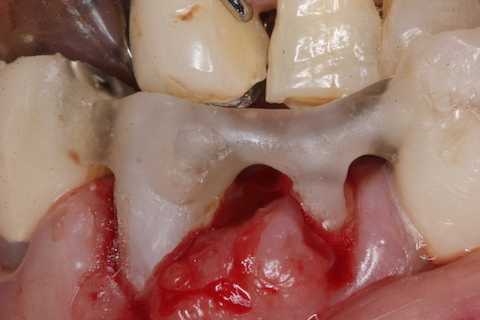

前回 ​のつづきで、再植と化粧をする。さすがに歯なしでは寂しい。

普通にズブズブと抜歯窩に再建した歯根を挿入する。

あとは接着固定しながら、歯冠を再建していく。